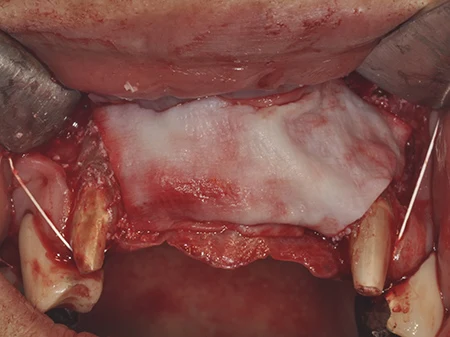

移植した部分をブタ由来のコラーゲンの膜で保護します。

縫合して終了します。